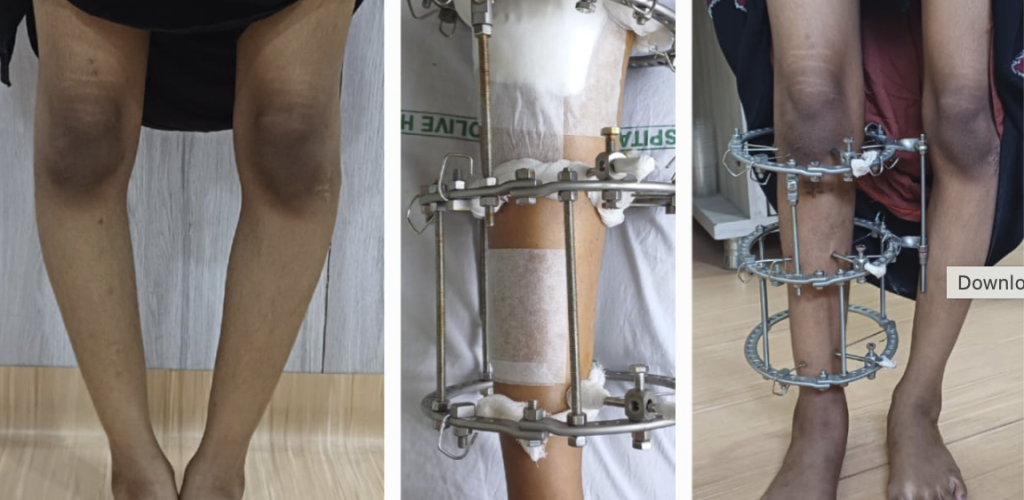

Corrective Osteotomy for Genu Valgum

Clubfoot Correction

Genu Varum Correction With Ilizarov

Neglected Clubfoot Correction Using Ilizarov